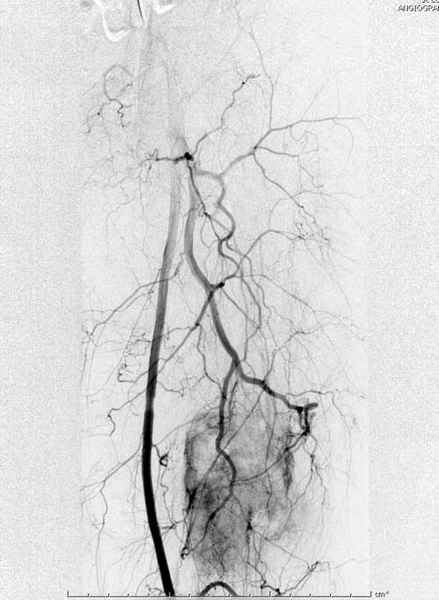

В зависимости от характера опухоли некоторые патологические переломы имеют риск кровотечения во время операции. Множественные литературные данные подтверждают, что надо проявить осторожность при интрамедуллярном остеосинтезе при неизвестных опухолях, особенно где имеется подозрение на Renal Cell Carcinoma. (RCC- hypernephroma) http://www.bonetumor.org/tumors/pages/page64.html

Для предупреждения кровотечения во время рассверливания, за день до операции провели эмболизацию сосудов питающий метастаз. http://radiology.rsnajnls.org/cgi/reprint/150/3/673.pdf (7-11, 12-15-16)